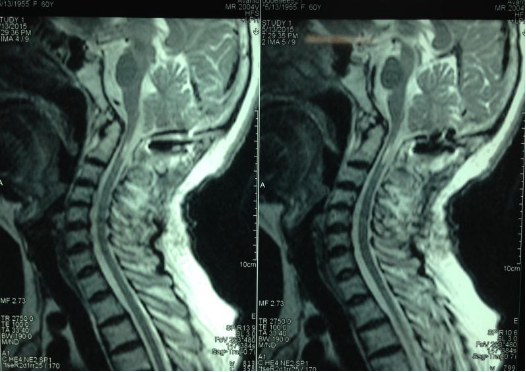

3影像学检查

手术前前屈位X光片寰枢椎脱位(寰齿前间隙7mm)。寰枢椎三维CT见寰枕融合,颅底陷入(齿状突位于钱氏线上14.2mm),右侧枢椎椎弓根发育狭小(小于2mm),磁共振显示小脑扁桃体下疝、颈髓损伤伴椎管狭窄。

4术前片子